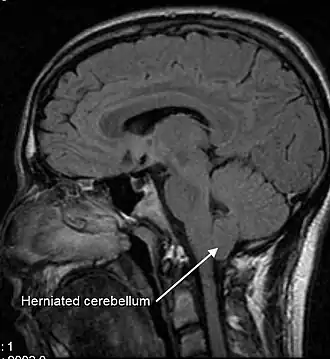

Le diagnostic est basé sur les antécédents médicaux du patient, un examen neurologique et l'Imagerie par Résonance Magnétique (IRM). L'IRM est l'examen de choix pour poser le diagnostic de la Malformation de Chiari. Ce type d'examen permet la visualisation des tissus neuraux tels que les amygdales cérébelleuses, la moelle épinière ainsi que les os et les tissus mous. La tomographie et la myélographie par tomographie étaient d'autres options utilisées avant l'avènement de l'IRM mais ce dernier est désormais l'examen de référence car malheureusement, la résolution et les modalités de la tomographie dite Computerized Tomography (CT) ne permettaient pas de poser le diagnostic d'une éventuelle syringomyélie ou d'autres anomalies neurales.

Par convention, les amygdales cérébelleuses sont mesurées par rapport à la ligne de Mac Rae, par IRM en coupe sagittale en T1 ou des images CT en sagittale. La distance sélectionnée de la jonction utilisée est quelque peu arbitraire car toute personne n'est pas nécessairement symptomatique en dépit d'une position anormale des amygdales cérébelleuses et la probabilité des symptômes et de la présence d'un syrinx croissent à mesure que l'engagement dans le foramen magnum est grand. Cependant, la norme est quand le déplacement des amygdales est supérieur à 5 mm. Certains considèrent qu'entre 3 et 5 mm de déplacement comme étant aux limites car des symptômes et un syrinx peuvent apparaître[8],[9],[10].

Les signes pathologiques et un syrinx peuvent apparaître dans le cas de déplacements d'amygdales cérébelleuses inférieurs à 5 mm. Une étude a montré peu de différence dans la position des amygdales cérébelleuses entre l'IRM couchée standard et l'IRM verticale pour les patients sans antécédents de traumatisme cervical[11]. L'investigation neuro-radiologique est utilisée pour d'abord exclure toute condition intracrânienne qui pourrait être responsable d'une hernie amygdalienne. Les diagnostics neuro-radiologiques évaluent la gravité de l'encombrement des structures neurales dans la fosse crânienne postérieure et leur pression contre le foramen magnum. Chiari 1.5 est un terme utilisé lorsque les hernies du tronc cérébral et des amygdales à travers le foramen magnum sont présentes[12].